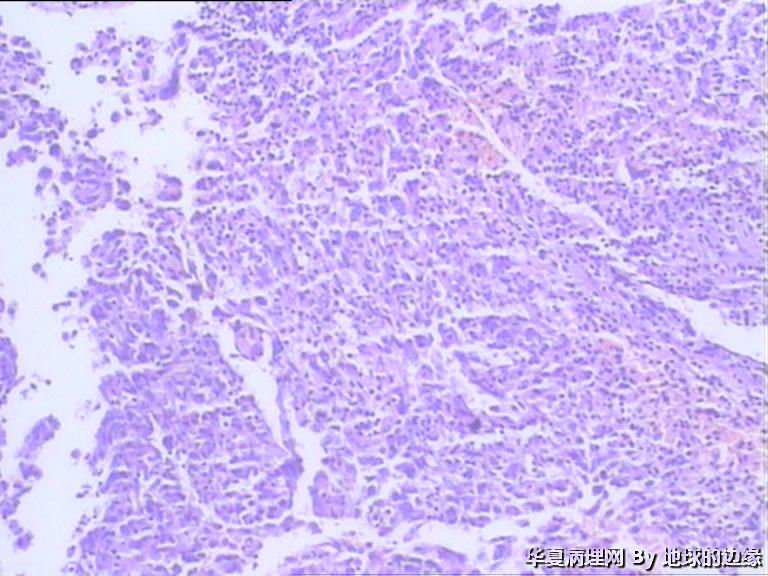

病人女性,48岁

MRI示:右肱骨肿瘤待排,包块大小为10x8cm,活动度差,边界欠清,鱼肉组织(白色),肿块侵犯至骨外    组  织。

• 右肱骨肿瘤待查图1

图1

恶性。是转移还是原发,是骨肉瘤还是浆母?需要进一步资料并标记。

考虑肉瘤,转移癌也排除一下吧